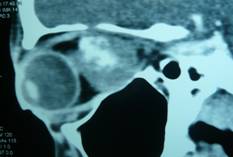

| CT scan evidencing intraconically growing hemangioma | |

- Vascular lesions: hemangiomas (the most common)